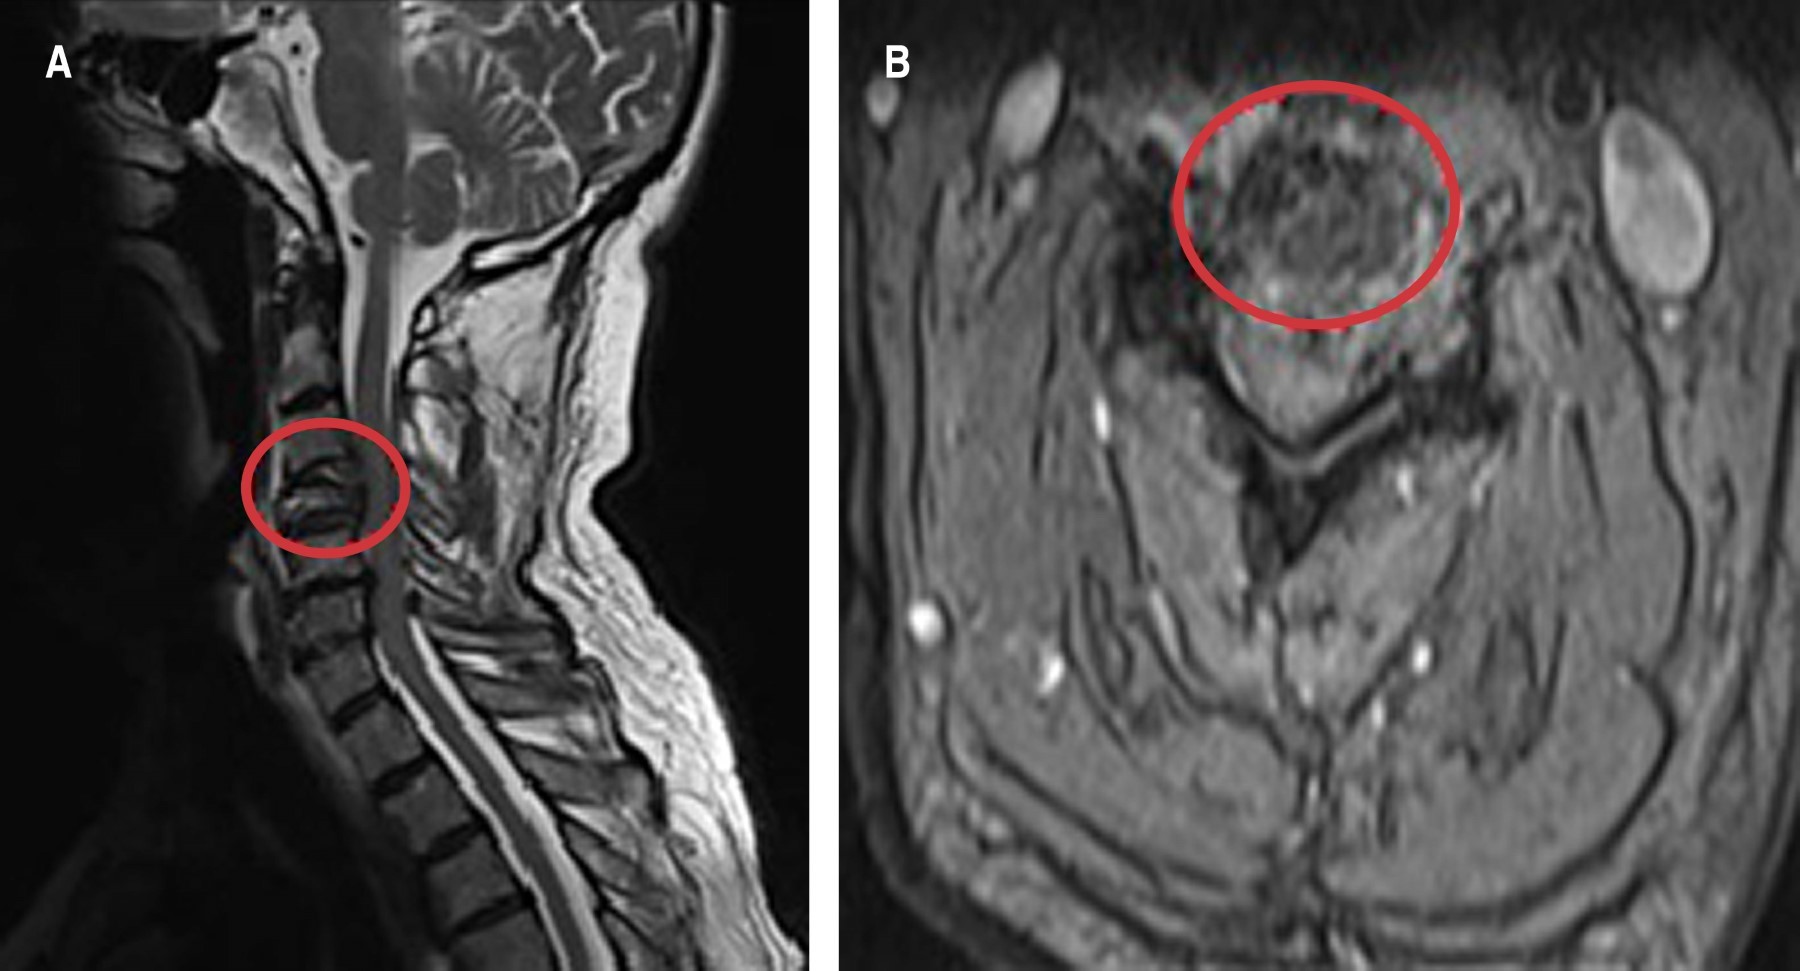

A la evaluación física paciente presenta pérdida de fuerza en dermatoma C6, con reflejos osteotendinosos 2/4, signo de Hoffmann negativo, prueba de Spurling positiva. Se realiza resonancia magnética cervical, evidenciando compresión medular en C3-C4, C4-C5, C5-C6. En resonancia magnética (RM) y tomografía axial computarizada (TAC) cervical se reportó lesión osteolítica del cuerpo vertebral C4, que involucra apófisis transversa izquierda, con componente de tejido blando que estrecha el foramen izquierdo (Figura 1A-B).

Se describe una presentación y diagnóstico inusual de HCC en la que el paciente debutó con mielopatía compresiva a nivel de las vértebras cervicales C3-C4, C4-C5, C5-C6.